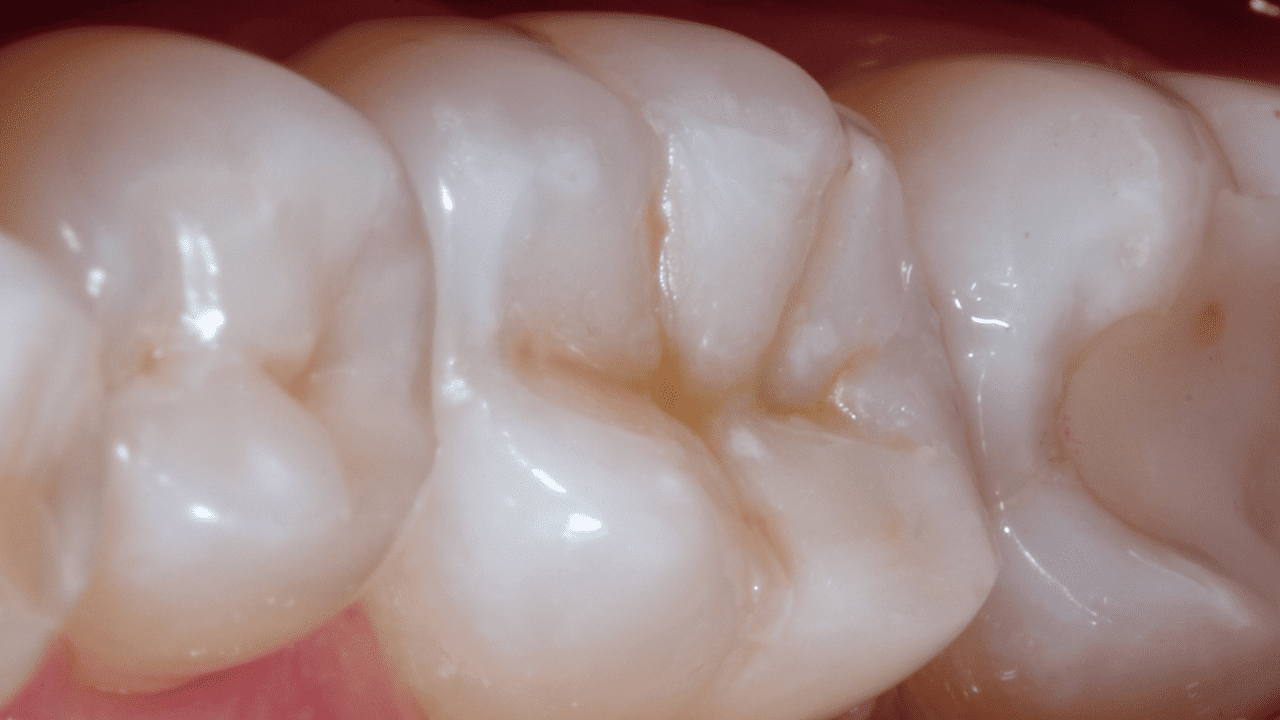

Case: A 38 year old male patient presented a failed Class II DO composite restoration on a lower molar. After radiographic and clinical examination, the patient was anesthetized, and the old failed restoration, as well as the caries lesion, was removed. The Class II DO cavity restoration was performed using an optimized approach.